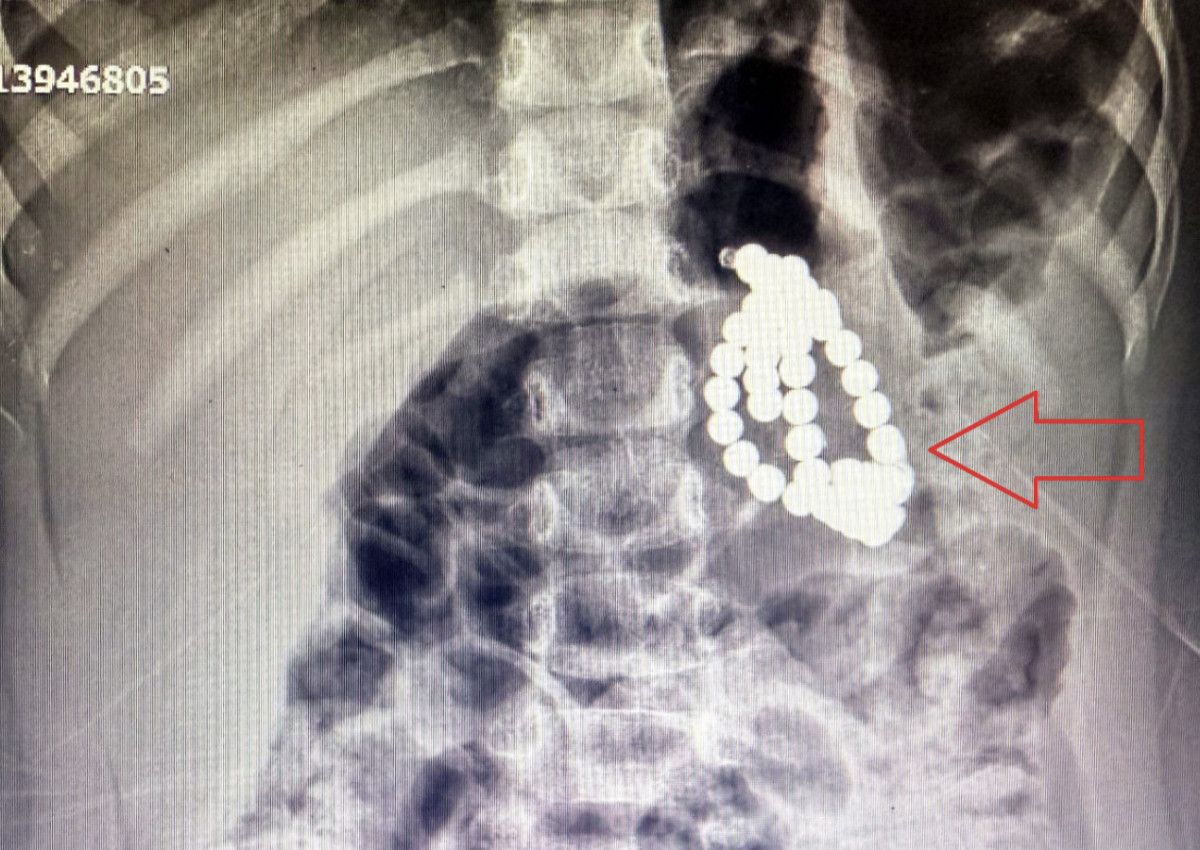

Çekilen röntgende, mide ve bağırsaklarında boncuk gibisi yabancı cisimler tespit edildi.

Aile kızlarının kolye ya da bileklik yuttuğunu düşünürken, hekimler manyetik boncuklardan şüphelendi.

Yuttuğu cisimlerin mıknatıslı boncuk olduğu anlaşılan Berfin, ivedilikle ameliyata alındı ve Çocuk Cerrahi ve Gastroenteroloji takımlarının birlikte girdiği 5 saat süren ameliyatla sindirim sisteminden 66 adet manyetik boncuk çıkarıldı.

Endoskopi sırasında midede 3, bağırsaklarda 2 delinme ve yapışıklık da tespit edildi.

3 yaşında bir kız çocuğu. Acile mide bulantısı kusma şikayetiyle başvurdu. Röntgende, karında çok sayıda boncuğa emsal yabancı cisme rastlandı. Aile daha çok boncuk, bileklik biçimi plastik birşey yuttuğunu düşünüyordu. İmaja baktığımızda, son vakitlerde çok sık rastladığımız magnet boncuk yutma hadiselerine benziyordu.

Ameliyata Gastroentrologlarla bir arada girdiklerini anlatan Çakmak, mideden 34 adet manyetik boncuk çıkarıldığını kaydederek kelamlarını şöyle sürdürdü:

Endoskopi esnasında midede üç yerde delinme olduğunu gördük. Sonra cerrahi kısma geçtik. Midede, ince bağırsakla birleşmiş halde fistül dediğimiz, yapışıklığa delinmeye bağlı, üç yer tespit ettik. Tıpkı biçimde ince bağırsakla kalın bağırsağın başlangıç kısmında da iki yerde delinme meydana gelmişti ve bağırsaklar birbirine yapışmıştı.

Bunlar çok uzun müddetli yapışıklıklardı, yaklaşık 6-7 aydır o manyetik boncuklar midede ve bağırsaklarda birbirine yapışmış halde duruyordu. Toplam 66 tane manyetik boncuk çıkardık. Hastamızın delinmiş organlarını laparoskopik olarak onardık.